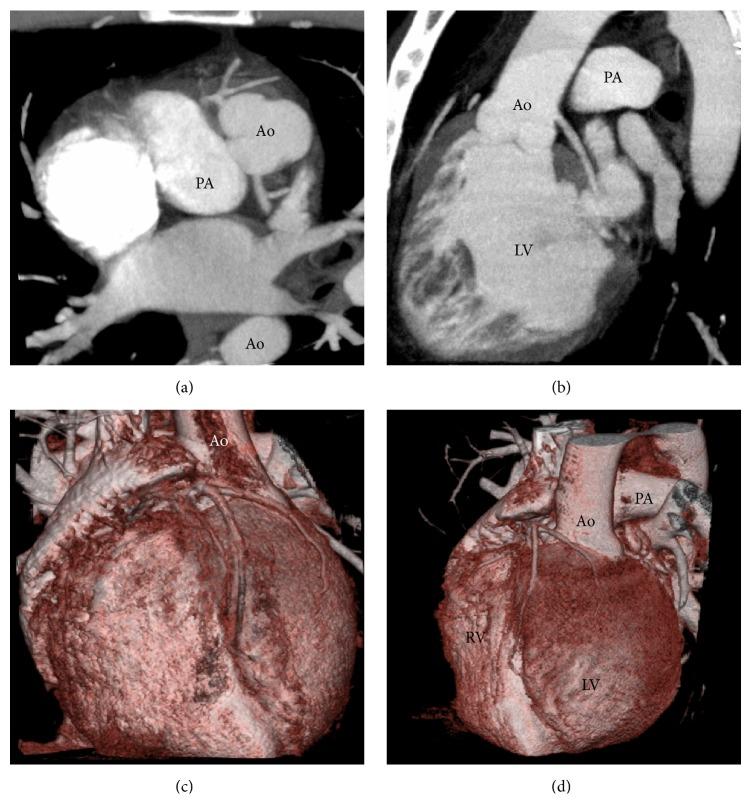

Left ventricular noncompaction (LVNC) is a myocardial disorder probably due to the arrest of normal embryogenesis of the left ventricle. It could be isolated or associated with other extracardiac and cardiac abnormalities, including coronary artery anomalies. Despite the continuous improvement of imaging resolution quality, this cardiomyopathy still remains frequently misdiagnosed, especially if associated with other heart diseases. We report a case of LVNC association with both malposition of the great arteries and a very original coronary artery pattern.

左心室心肌致密化不全(LVNC)是一种心肌疾病,可能是由于左心室正常胚胎发育停滞所致。它可以是孤立存在的,也可与其他心外和心脏异常相关,包括冠状动脉异常。尽管成像分辨率质量不断提高,但这种心肌病仍经常被误诊,尤其是与其他心脏病相关时。我们报告一例左心室心肌致密化不全合并大动脉转位及一种非常罕见的冠状动脉形态的病例。